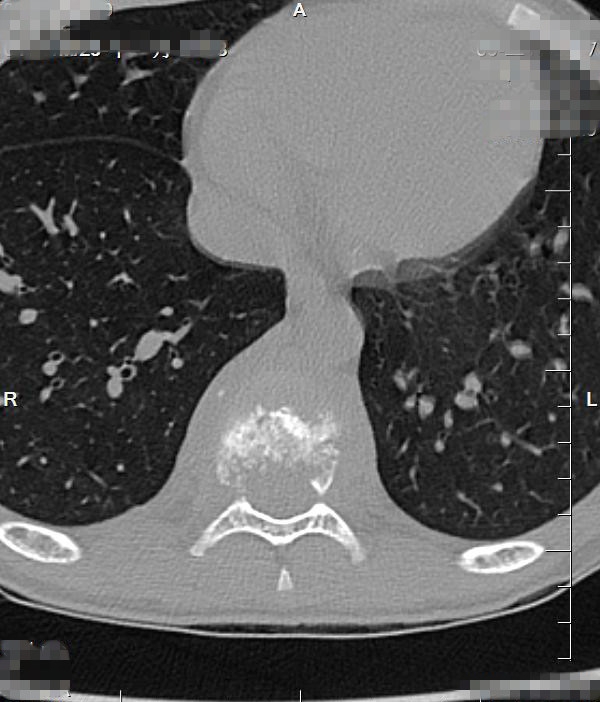

入院CT:结合MRI考虑,T9椎体病理性压缩性骨折,双侧椎弓根骨折,伴周围软组织感染性改变。

CT

椎体脊柱病变可单发或多发,椎体可呈楔形或完全变扁呈钱币状,亦可呈溶骨性破坏,很少累及相邻的椎体椎间隙。CT及MRI可多层面显示椎体及附件的溶骨性破坏椎体的溶骨性破坏。常累及一侧椎弓根,同时还可清楚显示椎旁的软组织肿胀和包块,亦可显示椎管内受累的情况。